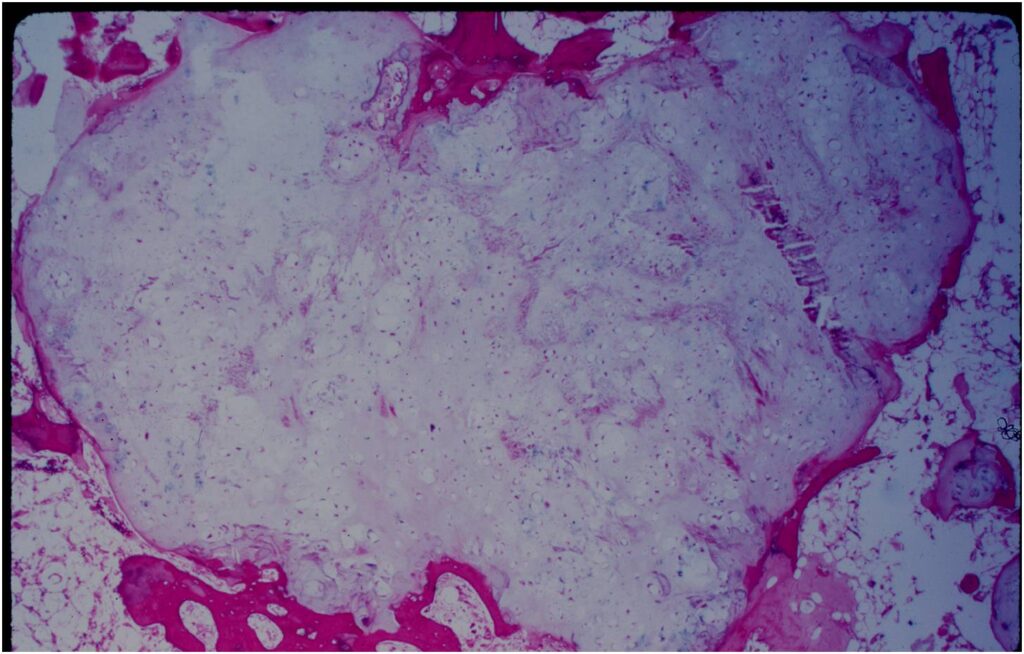

- Rests of hyaline cartilage with a lobular growth pattern

- Cells are within lacunae

- Hypocellular with cells spaced apart separated by matrix

- Cells have small nuclei and are similar size and shape (no pleomorphism)

- No mitotic figures

- The matrix has a ground glass basophilic appearance

- Enchondromas are well defined lesions with cartilage arranged in lobules that are separated by fibrovascular septa

- Enchondral ossification may occur around periphery of lobules and when calcified appear as “Rings and Arcs” on X-rays

- Cells are in lacunae and have small dark nuclei

- Low cell count, cells appear bland with few chondrocytes and are similar size and shape

- No entrapment or destruction of trabeculae